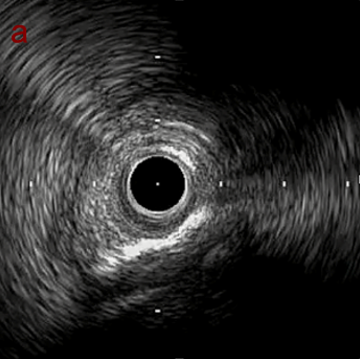

IVUS after OAS high speed 3回追加

IVUS imaging after high speed 3回追加

a,b,cの十分な石灰化のsanding。

High riskのbias所見へと変わっていったdの部位に関してはpinpoint OASを行うことでinjuryなく治療できた。

Cutting + DCBの方針に。